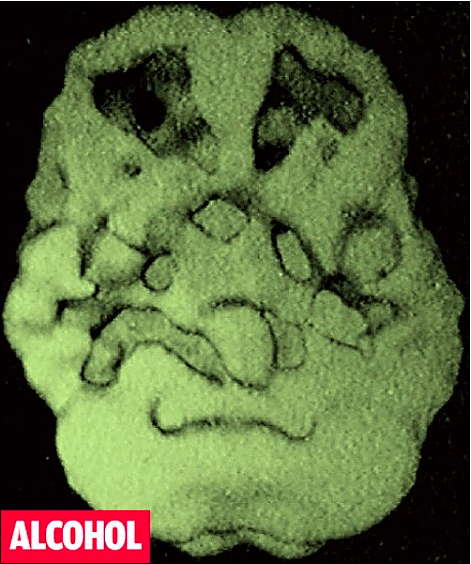

The same rules apply to any substance you put into your body, it doesn’t matter if it’s alcohol, drugs, or caffeine. Excess intake in any form will always become a problem. Outward physical signs of deterioration are only one sign of an issue. However, anything that gets put into your body has an effect, even if you can't see it. If you do enough of anything the effects on your brain can be quite large. If you don’t believe me, then just check out the images below that depict the end result of alcohol and drug overuse. The SPECT scans below show lack of blood flow to different areas of the brain after repeated use of a substance. Although we might not be fully aware of the damage these substances are causing, alcohol and drugs restrict blood flow to certain parts of the brain. If certain areas like the prefrontal cortex don’t have access to blood then bad decisions will inevitably result. This is due to the fact that blood is “food” for the brain. When this "food" supply is cut off by amygloid plaque buildup, caused by alcohol and drugs, then important areas of your brain will suffer. Although no outward signs to your body will be apparent, the symptoms of that buildup can be identified in a person's ability to function. Some examples of those symptoms may include legal issues, divorces, depression, anxiety, or relationship issues. All of this is very bad news for your brain if you use alcohol or drugs regularly. The good news, however, is that if you stop using substances or cut back dramatically the “pipes” (blood vessels) in your brain that have been clogged will eventually become clear again.

This SPECT scans shows a marked decrease in blood flow to prefrontal cortex. Too much or too little activity in this area makes you unpredictable and moody.